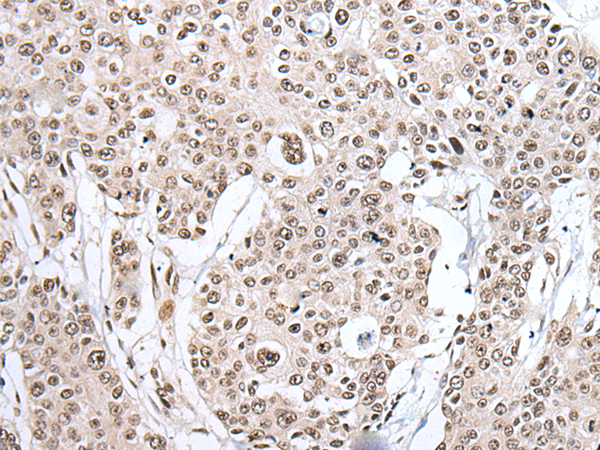

ELISA, WB, IHC

IHC positive control:

Human esophagus cancer and human liver cancer

IHC Recommend dilution:

25-100